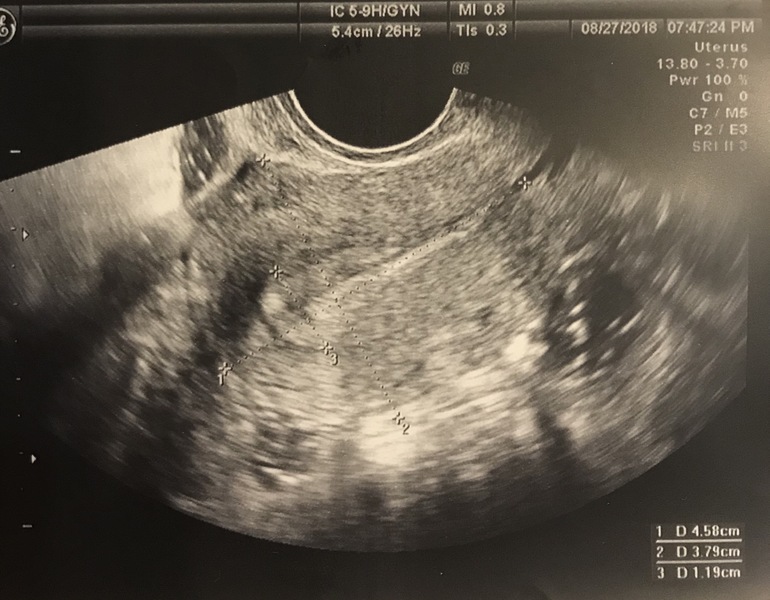

УЗИ: полип, бхб

Замершая беременностьКто нибудь разбирается в УЗИ и полипах? По УЗИ подозревают эндометрит и полип. После замершей весной(генетика), эндометрий растёт, но теперь видимо плохой..начали планировать в июле, и 2 бхб подряд( хотя в этот цикл вообще на УЗИ сказали что овуляции не было). И в оба раза с 11 дпо коричневая мазня. В этот раз пила дюфастон, мазня к 13 дпо прекратилась, но все равно бхб. Генетику только ещё будем проверять, дорого все сразу.. но почему то мне думается что ребёнок просто не мог просто прикрепится оба раза.. Собираюсь идти платно на гистеру, не хочу терять время. Что думаете?